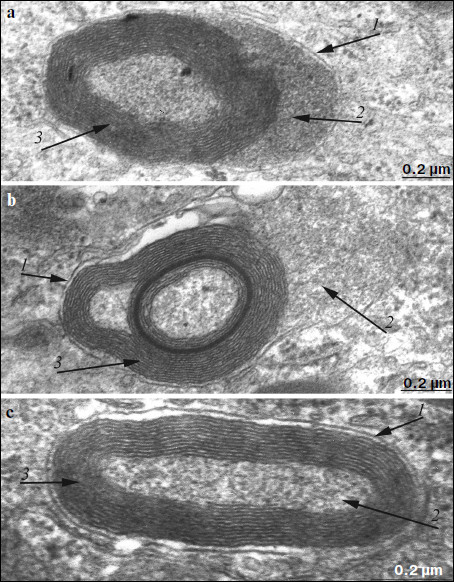

Fig. 8. Ultrastructure of separate electron-dense cytoplasmic inclusions in pigment epithelium of 11-month-old OXYS rats treated with SkQ1 drops (250 nM) under high magnification (a, b, c – different structural variants). Arrows: 1) restricting membranes; 2) granular matrix; 3) membrane concentric layers.

Electron microscopy showed that after treatment with SkQ1 drops, the ultrastructure of pigment epithelium cells changed significantly. An aggregate of numerous electron-dense structures looking as a strongly developed continuous layer, passing through all pigment epithelium cells, was revealed in apical cytoplasm of the latter (Fig. 6). It is also necessary to note that in separate regions of the pigment epithelium we detected the appearance of a second layer of cells with the strongly developed system of mitochondrial reticulum (Fig. 7). In this case, electron-dense structures were localized mainly in the upper layer of pigment epithelium cells. Our results show that, like in Wistar rats, morphology of these cytoplasmic inclusions is very diverse. They contain lipofuscin granules, but mainly this layer contains different structures. They are oval electron-dense structures filled by an electron-dense substance. We managed to find that separate such structures are mitochondria partially filled by electron-dense material. Besides, organelles of unusual ultrastructure are present in cytoplasmic inclusions. They are of round or spherical shape, surrounded by a single-layer membrane, its internal space filled by granulated matrix and tightly adjacent concentric membrane layers (Fig. 8). The origin and functional significance of these structures are still unknown.